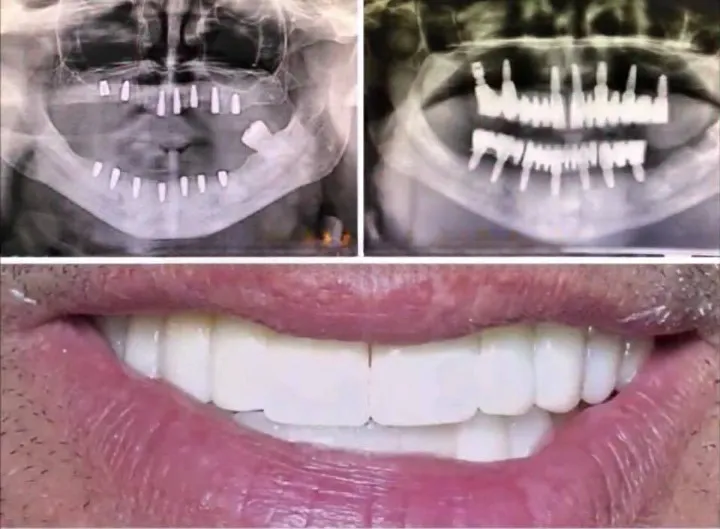

Chirurgie Régénératrice

Reconstruction de l'os et regeneraiton tissulaire grâce aux biomatériaux et membranes. Redonner du support aux dents déchaussées.